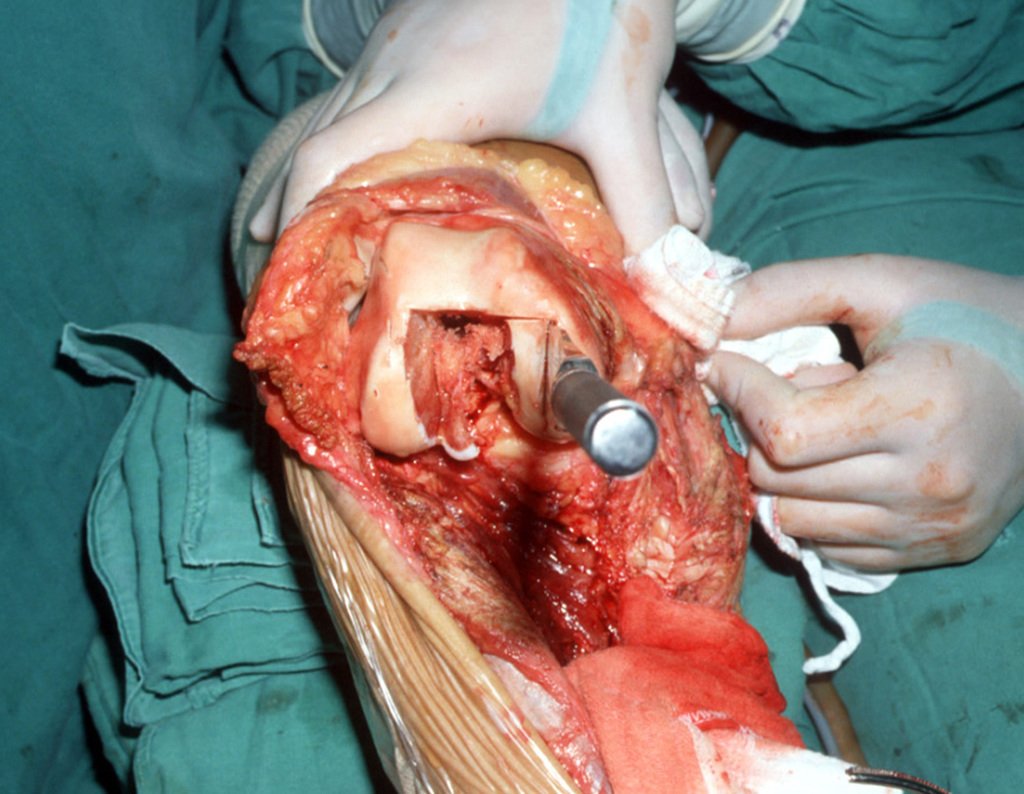

La resección se realizó en bloque, el 03/06/1989, con extirpación de toda el área afectada, figuras 4 a 15.

La reconstrucción se realizará con la prótesis diseñada especialmente para este paciente, fabricada en polietileno y acero inoxidable y con un componente intraepifisario en el fémur, figuras 13 a 15.

El cartílago patelofemoral debe preservarse tanto como sea posible. Con la cureta localizamos el canal femoral, figura 16. Se colocará el componente femoral entre los cóndilos femorales. Para ello es necesario realizar una osteotomía rectangular, que permita el posicionamiento adecuado del componente, figuras 17 y 18.

Esta fue la primera prótesis intraepifisaria que realizamos. En ese momento, en 1989, no teníamos guías de corte y el cirujano hacía los cortes a mano, usando su habilidad para seguir los parámetros clínicos.